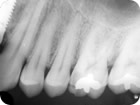

Tratamento Endodôntico

Tratamento Endodôntico 1

Tratamento Endodôntico 2

Tratamento Endodôntico 3

Tratamento Endodôntico 4